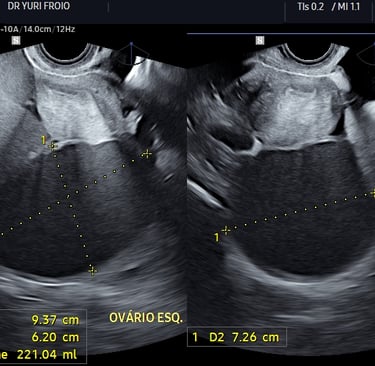

A ultrassonografia pélvica é fundamental para a avaliação do útero, ovários e outras estruturas da pelve feminina. A via transvaginal oferece imagens mais detalhadas e é amplamente utilizada na investigação de patologias ginecológicas.

Avaliação de cistos ovarianos;

Investigação de dor pélvica e endometriose;